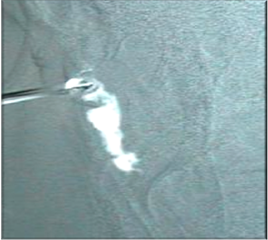

Otra prueba, es la radiológica. Se llama Dacriocistografía. La técnica es la misma que la irrigación descrita previamente pero con un contraste biológico vegetal. Se realizan dos o tres placas para ver el paso del contraste y así evaluar mejor su recorrido. No es una prueba imprescindible.

![]() |

| Dacriocistografia.Se aprecia que el contraste, en blanco tiene un stop |